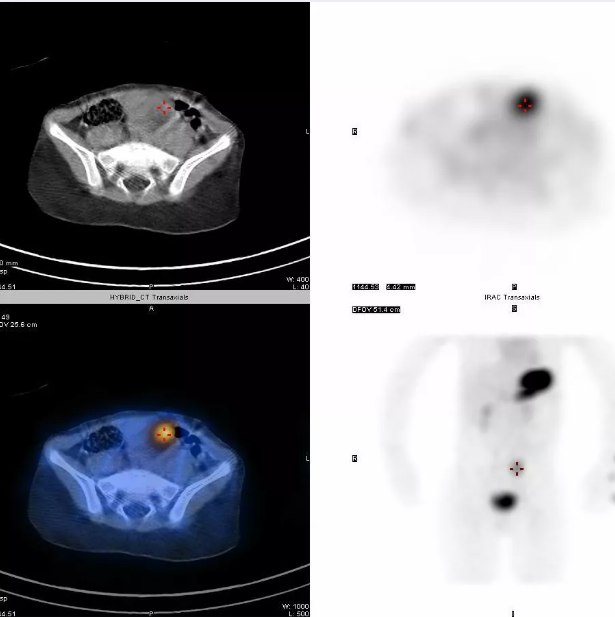

异位胃黏膜显像

在胃以外消化道组织中生长的胃黏膜组织,能够摄取和浓聚高锝酸盐显像剂,能够诊断:梅克尔憩室、Barrett食管、小肠重复畸形。

▲异位胃黏膜显像(梅克尔憩室显像阳性)